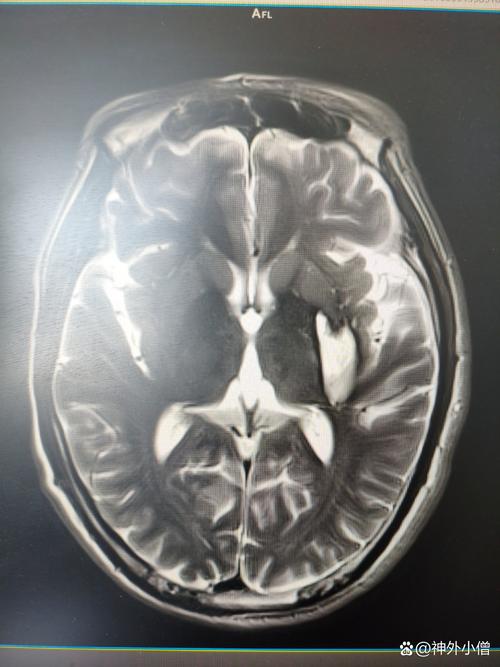

(图片来源网络,侵删)